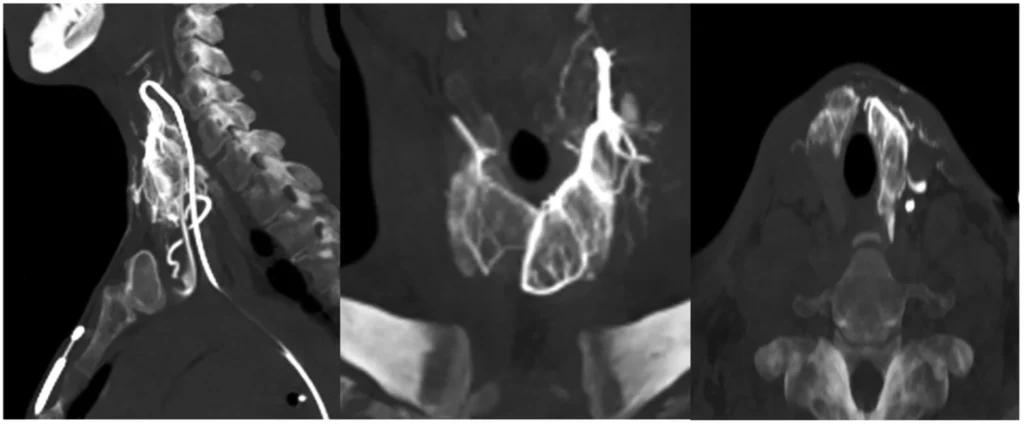

This procedure is really different from thyroid surgery. You do not get a cut in your neck and the thyroid gland is not taken out. What happens is that a small hole is made, in the groin area or sometimes the wrist and a thin tube is put through the blood vessels. The doctor uses imaging to guide the tube to the arteries that go to the thyroid. Then the doctor puts material into the arteries to stop the blood flow to the parts of the thyroid that are causing problems. The doctor is very careful to stop the blood flow to the bad areas and not to the healthy tissues, around them. The thyroid procedure is done to help the thyroid gland. The doctor uses the special material to help fix the thyroid.

How Thyroid Artery Embolization Works

To understand thyroid artery embolization think about this: thyroid tissue needs blood to grow and work properly. The thyroid gland has a lot of blood vessels. Some thyroid problems can even have blood vessels in certain areas. Thyroid artery embolization is a way to slow down the blood flow, to the thyroid tissue that is causing problems. It does this in a careful and controlled way. Thyroid artery embolization helps by reducing blood flow to the targeted thyroid tissue.

The thyroid treatment process usually begins with checking if someone is a candidate through a medical check and pictures of the inside of the body.

During the treatment the doctor uses pictures to help guide a tube to the thyroid arteries.

The doctor finds the branches that bring blood to the bad part of the thyroid gland the part that is causing problems or is abnormal.

Then the doctor puts in tiny particles these particles are called embolic particles to slow down the blood flow, to the bad part of the thyroid gland to the abnormal tissue of the thyroid gland.